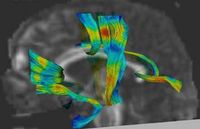

Fiber Tract Modeling, Clustering, and Quantitative AnalysisThe goal of this work is to model the shape of the fiber bundles and use this model description in clustering and statistical analysis of fiber tracts. More... | |

DTI Fiber Clustering and Fiber-Based AnalysisThe goal of this project is to provide structural description of the white matter architecture as a partition into coherent fiber bundles and clusters, and to use these bundles for quantitative measurement. More...